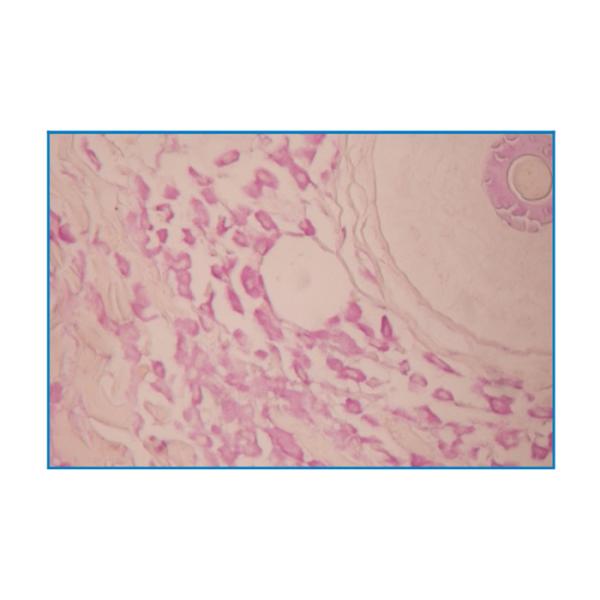

Mast Cell Stain

(Aldehyde fuchsin-OG6 staining method)

Intended for staining examination of histological mast cell.

Mast Cell Stain (Aldehyde fuchsin-OG6 staining method) Images |